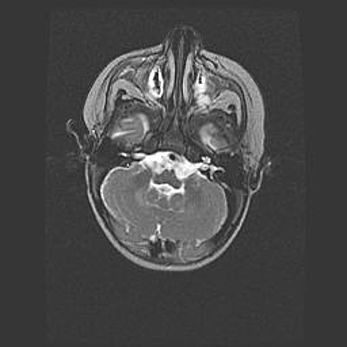

Аномалия Денди-Уокера – это порок развития головного мозга, для которого характерна триада симптомов: гипотрофия или аплазия червя мозжечка и/или полушарий мозжечка, расширение четвёртого желудочка с формированием ликворной кисты задней черепной ямки, гипертензионная гидроцефалия различной степени.

Гипоплазия мозолистого тела относится к дефектам внутриутробного этапа развития мозговой ткани, возникающим в процессе закладки структур головного мозга, что происходит на начальных этапах развития эмбриона.